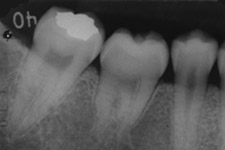

4年後

移植後4年。親知らずが第一大臼歯の代わりを担っています。

4年後。移植後に根が少し成長しているのが分かります。歯の神経もつながっています。